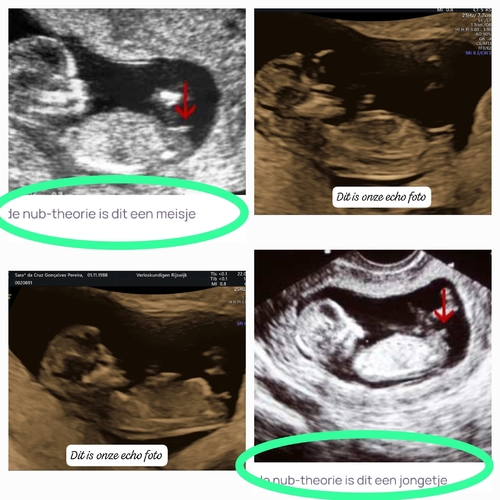

Het bovenste streepje is denk ik de navelstreng en dat onderste streepje daar pas je de nubtheorie op toe. Dat onderste streepje wijkt wel iets af naar boven dus in deze zou je kunnen zeggen hey word een jongen. Bij een meisje schijnt hey echt horizontaal te liggen maargoed het is maar een theorie

Onder de navelstreng zie je inderdaad dat de nub naar boven wijst. Plaats je foto ook eens in het algemene nub theorie topic :) weet zeker dat je alleen 馃挋馃挋馃挋 krijgt 馃グ